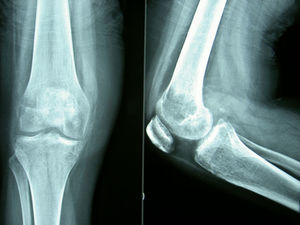

Horas después de realizarse estas pruebas, la paciente sufrió una caída fortuita, refiriendo de forma inmediata dolor intenso e impotencia funcional en la rodilla derecha. El estudio radiológico urgente mostró una fractura patológica supracondílea del fémur derecho (fig. 3).